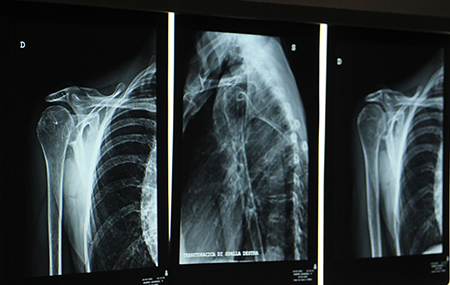

In Habilita Casa di Cura I Cedri è stato attivato il nuovo ambulatorio di ortopedia specifica per le patologie di spalla. L’équipe vede la presenza del Dr. Paolo Rolla e del Dr. Mario Rossoni. Entrambi gli specialisti, già presenti anche nella sede Habilita di Acqui Terme, ora operano anche nella sede di Fara Novarese (No). Abbiamo chiesto al Dr. Rolla di illustrare quali sono le patologie più frequenti per le quali si rende necessario un intervento chirurgico alla spalla.

“Le patologie della spalla che incontriamo con maggiore frequenza – spiega il Dr. Rolla – sono quelle legate alla cuffia dei rotatori (spalle dolorose con sofferenza della cuffia, fino alla rottura della cuffia dei rotatori), problematiche al tendine del capo lungo del bicipite che possono interessare sportivi, lavoratori manuali e casalinghe. Ci occupiamo poi di interventi relativi all’instabilità di spalla che vengono effettuati sia in artroscopia che a cielo aperto a seconda delle condizioni primarie della patologia: se abbiamo un’instabilità determinata dal cedimento dei tessuti molli con pochi episodi di lussazione allora interveniamo con la chirurgia artroscopica, in caso di revisione o di danni ossei si effettuano operazioni a cielo aperto con trapianto osseo. Abbiamo poi tutta la patologia degenerativa artrosica che richiede invece un trattamento con sostituzione articolare protesica”.

“La persona che ha una spalla dolorosa può nascondere, dietro una sintomatologia che potrebbe essere riconducibile ad una tendinopatia, delle patologie più importanti. Ad esempio, mi è capitato spesso di vedere negli ex culturisti dei casi di artrosi in età inusuale. A 40 anni ci troviamo di fronte ad artrosi tipiche di persone over 75. Questo è un problema legato frequentemente al sovraccarico articolare in età giovanile. Io consiglio quindi sempre di effettuare esami di diagnostica (radiografie e risonanza magnetica) per individuare con esattezza da dove nasce il problema. Spesso oggi le persone si presentano con una semplice ecografia che fornisce una visione molto superficiale dei problemi. Se una persona soffre di dolore alla spalla da oltre un mese e mezzo nonostante l’assunzione di antiinfiammatori, allora è il caso di verificare approfonditamente la situazione e capire come trattarla per risolvere il problema. I problemi lievi, che possono passare spontaneamente o con semplici trattamenti fisioterapici in un mese e mezzo, si risolvono, quelli che perdurano possono rivelarsi più seri di quanto appaia da un’ecografia”.